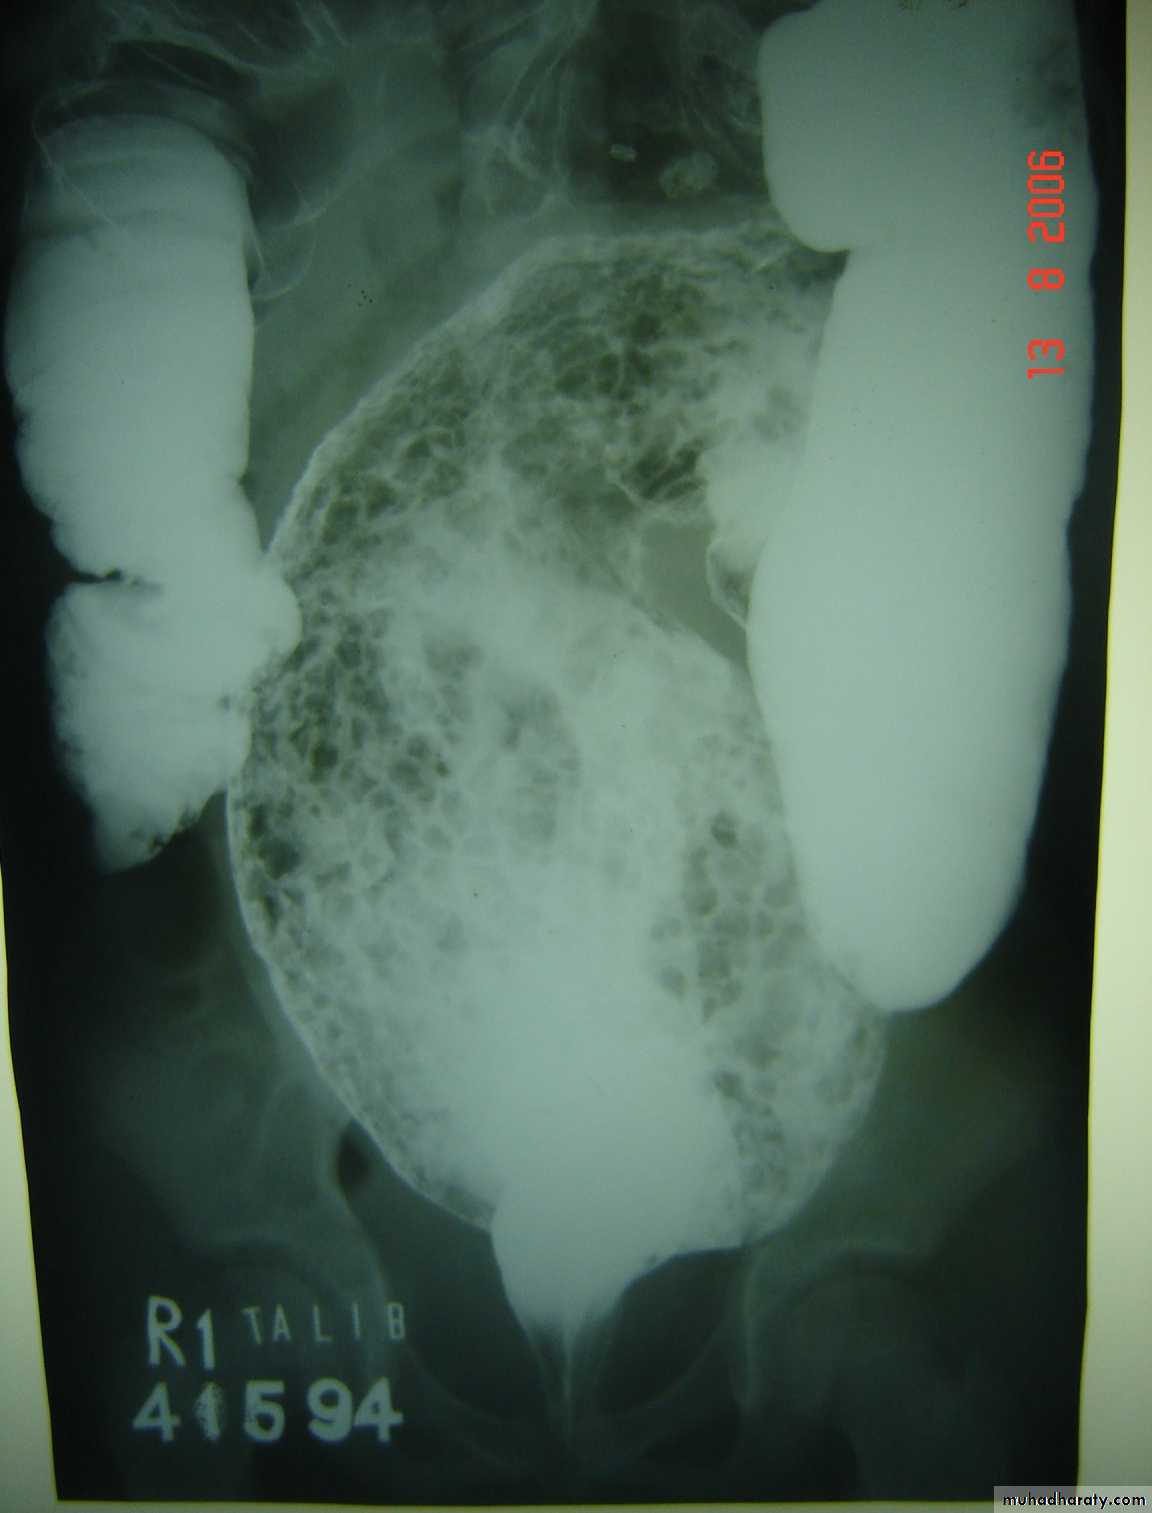

Intussusception

Pediatric surgery practical